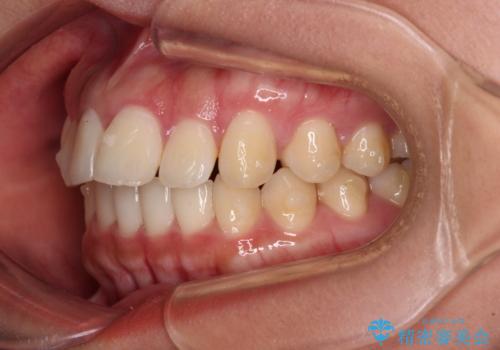

飛び出した上顎前歯 インビザラインで引っ込める

- 前歯の突出感を気にして来院された患者様です。

奥歯の咬み合わせは理想的な咬合に近く、インビザラインでも十分に対応できる歯列でした。

舌の突出癖を改善するためのトレーニングを行いつつ、上下歯列全体を後方に移動させ、更にはIPR(歯と歯の間を削る)によりスペースを獲得することで、口元の突出感を改善することとしました。